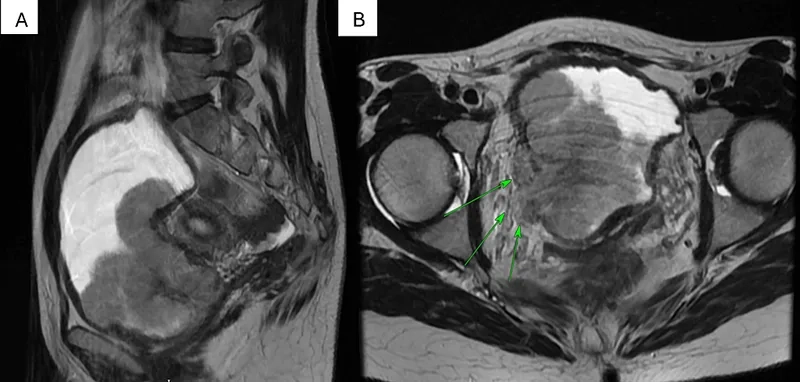

Image of the disease bladder cancer and other variables

A visual guide to the stages of bladder cancer